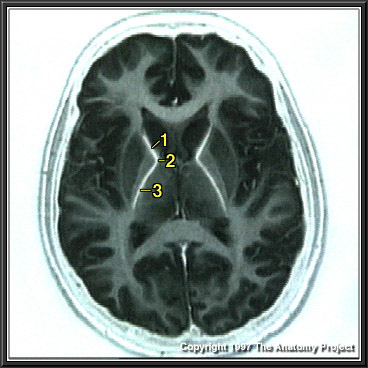

N1A5P5

803